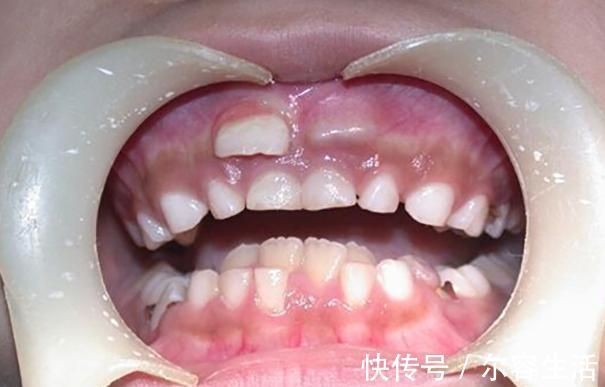

什么叫做“双排牙”?其实双排牙的主要原因是在换牙期,乳牙滞留,导致恒牙生长受阻,最后恒牙和乳牙并排而立。形成双排牙的主因有很多,糖果的关系并不大,和家长的喂养习惯相关。

一、孩子长出双排牙,一家人跟着着急何丽的女儿今年已经六岁多了,正值换牙时期,可是门牙始终都不松动,父母也没有太在意。可有一天女儿告诉妈妈,自己的门牙里面有两个硬硬的东西。因为门牙没有松动,恒牙没地方长,只能从旁边长出来了。何丽还是没有在意,等着孩子这几天门牙的松动,然后再给孩子拔掉。可是等了近一个多月,孩子的牙齿还是没有松动的迹象。于是何丽察觉到有一些不对劲了,就带着孩子去看了医生。医生说这两年双排牙的孩子越来越多,大部分都是因为饮食习惯不规范造成。

1. 孩子从小不吃硬的食物造成双排牙的极大可能,都是和饮食习惯有关,孩子在添加辅食开始,就是吃泥状食物。随后应该慢慢过渡到颗粒状食物,然后是小块状食物,最后孩子就能独立啃咬完整的食物。但是很多父母担心孩子不吃饭,于是都视线将食物处理好,孩子基本上接触不到稍硬的食材。最后导致乳牙得不到锻炼,就没有松动的迹象。2. 孩子自身的疾病还有些孩子是因为先天性的疾病,或者是继承恒牙出牙无力等等,这些都需要提前看医生,如果乳牙滞留的时间太长,就可以让医生拔出乳牙,让恒牙顺利长出来。